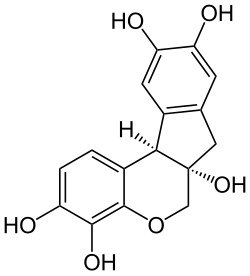

| Strukturformel | ||||||||||||||||||||||

Hämatoxylin oder Hämalaun ist eine natürliche chemische Verbindung aus der Gruppe der Indenochromene und der Polyphenole. Sie wird aus dem Kernholz des Blauholzbaums (Haematoxylum campechianum) gewonnen.

In seiner reinen Form ist Hämatoxylin farblos bis beige. Durch Oxidation mittels Luftsauerstoff (langsam) oder einem geeigneten Oxidationsmittel (z. B. Natriumiodat, Kaliumpermanganat, Wasserstoffperoxid oder Iod) entsteht in wässriger oder alkoholischer Lösung aus Hämatoxylin das ockerbraun gefärbte Hämatein. Diesen Vorgang nennt man auch (natürliche bzw. künstliche) „Reifung“. Hämatein ist ein leicht saurer Farbstoff. Die gewünschte färbende Wirkung wird erst durch den Zusatz mehrwertiger Metall-Kationen als Beize erreicht. In Gegenwart mehrwertiger Kationen, wie z. B. Eisen (Fe3+) und Aluminium (Al3+) bilden sich Farbstoffkomplexe durch Chelatbildung in der Stöchiometrie 1:1. Komplexe aus Hämatein und Alaunen werden dabei als Hämalaune bezeichnet. Hämalaune zeigen die typische dunkelblau-violette Farbe und werden auch als Hämatoxylinlack (eigentlich Hämateinlack) bezeichnet.

Durch Variation des pH-Wertes kann eine Selektivität für verschiedene Strukturen erreicht werden. Während bei einem pH-Wert von > 4,5 zahlreiche Zellstrukturen gefärbt werden, dominiert bei einem pH-Wert von 2–3 die Anfärbung von Zellkernen. Brasilin fehlt im Vergleich zu dem Farbstoff Hämatoxylin eine Hydroxygruppe.